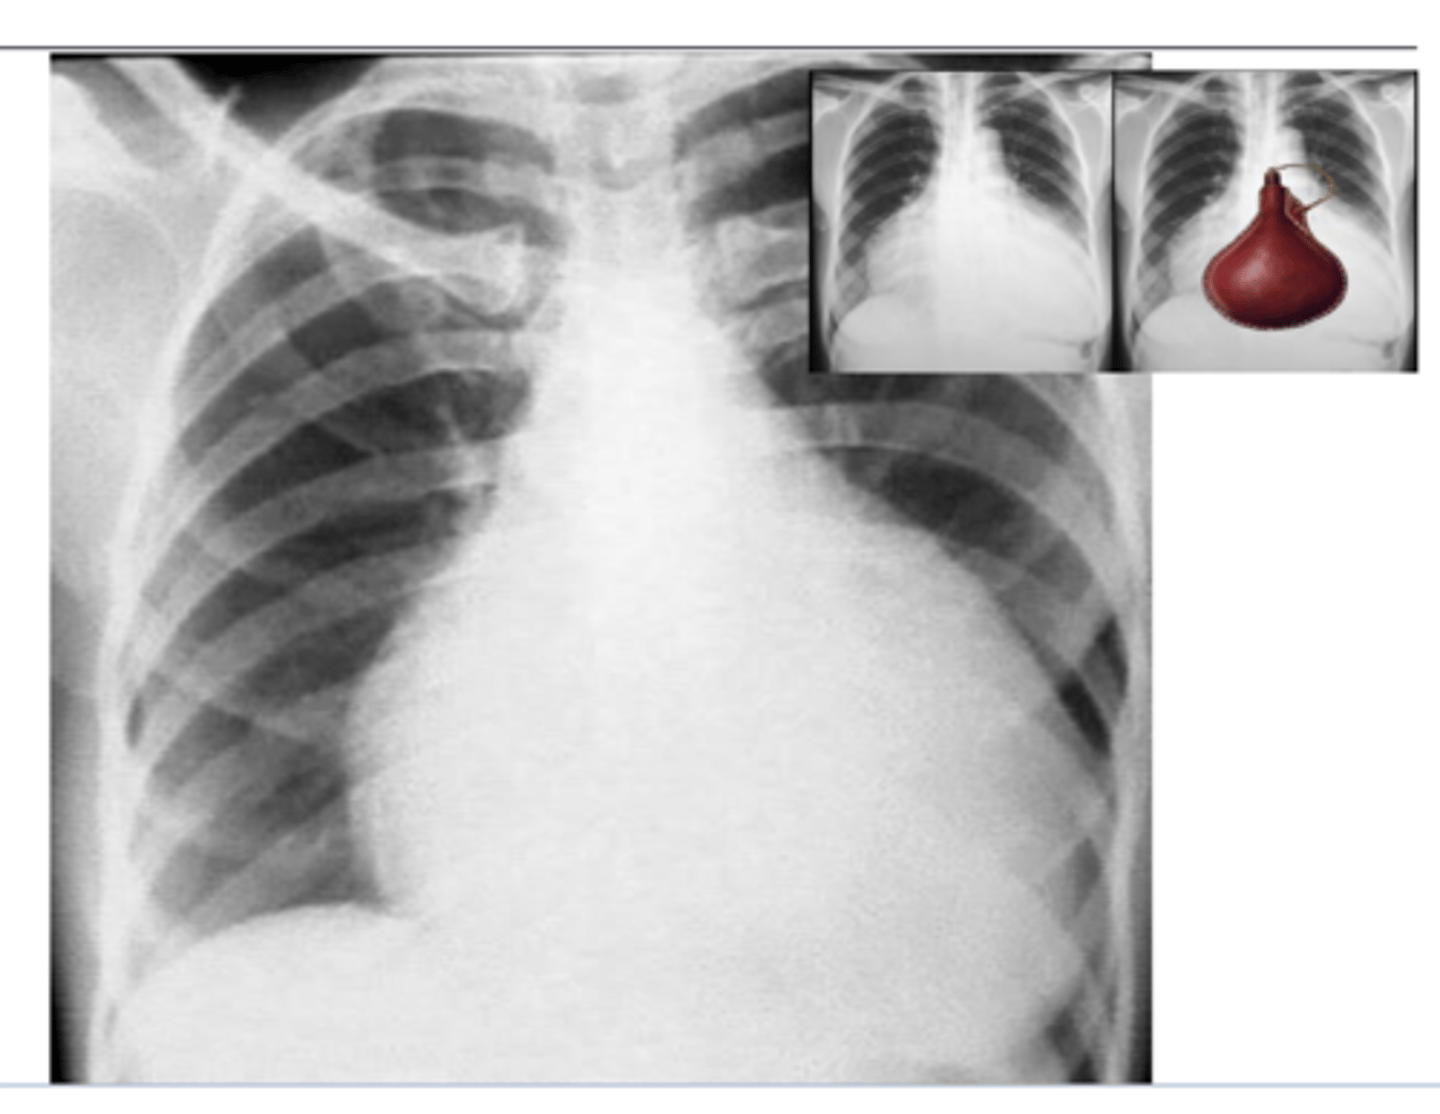

What is the typical appearance of pericardial effusion? Imaging of choice

Pericardial effusion causes an acute marked

enlargement with the heart appearing pendulous and very wide at the base – “water bag appearance.”

echocardiogram is imaging of choice (image here is x-ray)

<p>Pericardial effusion causes an acute marked</p><p>enlargement with the heart appearing pendulous and very wide at the base – “water bag appearance.”</p><p>echocardiogram is imaging of choice (image here is x-ray)</p>